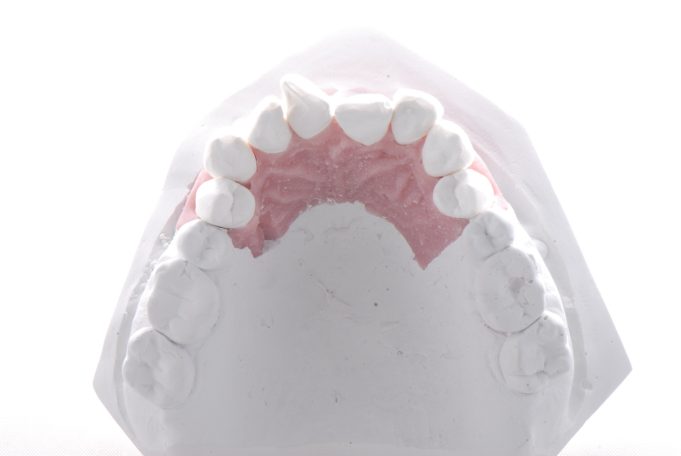

Teleskopierende Oberkieferbrücke mit Vorher- und Nachher-Situation des Patienten.

Teleskopierende Oberkieferbrücke. Wie die eigenen Zähne, aber einfach zu reinigen.